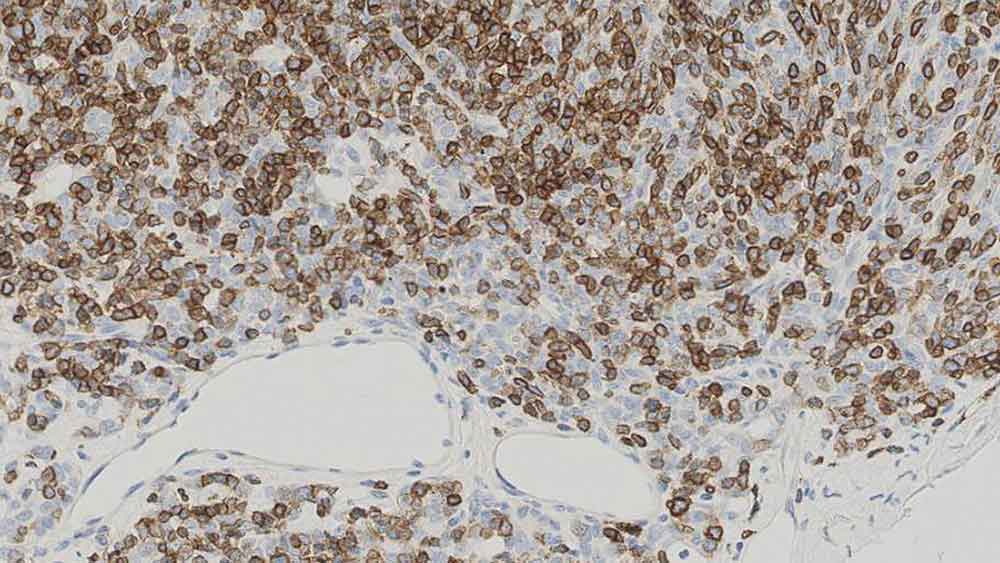

Human thymoma: immunohistochemical staining for CD1a. Note the neoplastic cells show a moderate to strong and distinct membrane staining reaction. CD1a: clone MTB1

Le CD1a est une protéine de 43 à 49 kD présente à la surface des cellules dendritiques et des thymocytes corticaux. On a montré que l'expression de l'antigène CD1a est utile pour différencier les cellules de Langerhans, des cellules présentatrices d'antigène présentes dans la peau et les épithéliums, des cellules interdigitées. Des études immunohistochimiques de l'antigène CD1a ont démontré une réduction des cellules de Langerhans épidermiques dans la maladie du greffon contre l'hôte, et la participation des cellules dendritiques CD1a-positives dans la formation des lésions athérosclérotiques et dans l'inflammation asthmatique. Le clone MTB1 détecte les thymocytes corticaux, les cellules de Langerhans de l'épiderme, les cellules interdigitées du derme et les cellules interdigitées de l'épithélium squameux stratifié des amygdales. Le clone MTB1 pourrait également détecter de petits groupes de lymphocytes en dehors des centres germinatifs des amygdales, indicatif d'une réaction croisée avec l'antigène CD1b. Le clone JPM30 détecte les thymocytes corticaux, les cellules de Langerhans de l'épiderme, les cellules interdigitées du derme, les cellules interdigitées de l'épithélium squameux stratifié des amygdales, mais marque aussi les canaux des glandes sudoripares du derme et les cellules épithéliales de l'intestin grêle, ce qui indique une réactivité croisée avec l'antigène CD1d.